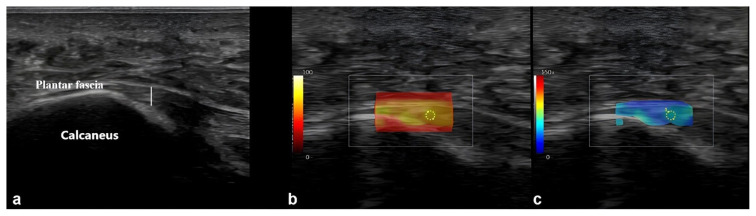

背景/目的:本研究的主要目的是比较健康志愿者和2型糖尿病(T2DM)患者足底筋膜(PF)和跟腱(AT)的厚度和刚度。次要目的是探讨无周围神经病变或足部溃疡、有周围神经病变或足部溃疡的T2DM患者中PF和AT的厚度和硬度与糖尿病病程(以月为单位)和血红蛋白A1c (HbA1c)水平之间的相关性。材料和方法:共纳入289名参与者,包括117名健康志愿者(A组)和172名T2DM患者(59.5%),年龄、性别和体重指数相匹配。T2DM队列分为三个亚组:B组(无周围神经病变或足部溃疡),C组(有周围神经病变)和D组(有足部溃疡)。采用超声(USG)和剪切波弹性成像(SWE)评估PF和AT特性,并分析其与糖尿病病程和HbA1c水平的相关性。结果:与健康对照组相比,T2DM患者表现出更大的PF和AT厚度,更低的僵硬度(p < 0.001)。各亚组中,D组PF和AT厚度最大,刚度最低,C组次之,B组次之(p < 0.001)。糖尿病病程、HbA1c水平和肌腱厚度呈正相关,而与肌腱僵硬呈负相关(均p < 0.001)。结论:USG和SWE显示,与健康个体相比,T2DM患者的PF和AT特性发生了显著变化,这些变化与糖尿病的严重程度和持续时间有关。

Material and methods: A total of 289 participants, including 117 healthy volunteers (Group A) and 172 T2DM patients (59.5%), matched for age, sex, and body mass index, were included. The T2DM cohort was stratified into three subgroups: Group B (without peripheral neuropathy or foot ulcers), Group C (with peripheral neuropathy), and Group D (with foot ulcers). Ultrasonography (USG) and shear wave elastography (SWE) were used to assess PF and AT properties, and correlations with diabetes duration and HbA1c levels were analyzed.